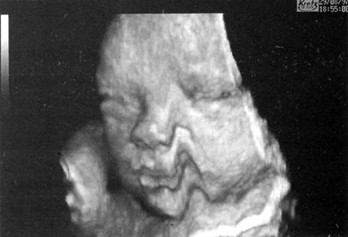

Врачи отмечают, что 3D и 4D УЗИ значительно изменили подход к пренатальной диагностике. Эти технологии позволяют получить объемные изображения плода, что помогает более точно оценить его развитие и выявить возможные аномалии. Специалисты подчеркивают, что 3D УЗИ предоставляет возможность увидеть детали, которые невозможно рассмотреть на традиционном 2D УЗИ, такие как форма лица и конечностей.

Объемное ультразвуковое исследование предоставляет детализированные анатомические изображения, которые недоступны при стандартном 2D-сканировании. Эта методика позволяет более точно установить эмбриональный возраст на ранних сроках беременности, а также своевременно обнаруживать аномалии развития сердца, лица, конечностей, головного мозга и позвоночника, обеспечивая высокую точность измерений исследуемых объектов.

Современные технологии ультразвукового исследования, такие как 3D и 4D УЗИ, вызывают множество обсуждений среди будущих родителей и медицинских специалистов. Многие отмечают, что 3D УЗИ позволяет получить объемные изображения плода, что делает процесс более наглядным и эмоциональным. Родители могут увидеть черты лица своего ребенка, что создает особую связь еще до рождения.